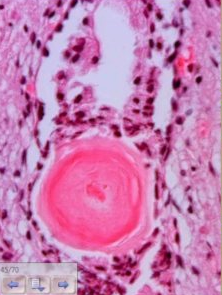

Corpora Amylacea, strongly suggests benign